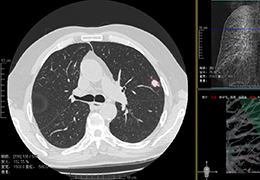

View X-Ray CT & MRI Scans Fast and Easily

Designed for surgeons, Pro Surgical 3D makes it easy to view patient scans quickly. Pro Surgical 3D facilitates the optimal 3D treatment and assessment workflows based on X-ray CT and MRI scans – and best of all, it’s FREE!

Traditional multi-planar slicing

Designed mainly for CT and MR DICOM modalities.

Multi-planar slicing.